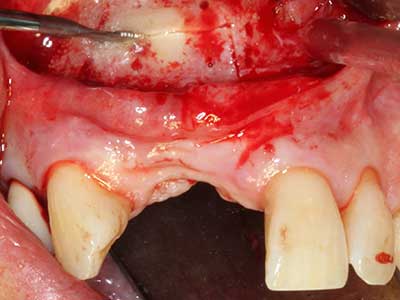

La piezochirurgia presenta altri vantaggi per quanto riguarda la raccolta di blocchi ossei. Oltre all'elevata precisione dell'osteotomia appena descritta, l'utilizzo di puntine per sega molto sottili permette di minimizzare in maniera significativa la perdita di materiale. È molto probabile che si verifichi una maggiore perdita di materiale durante la raccolta utilizzando puntine di strumenti più spessi, in particolare delle frese Lindemann (Lakshmiganthan, Gokulanathan et al. 2012). La separazione basale, necessaria in particolare per i trapianti di blocchi nella zona retromolare, viene semplificata grazie a seghe specificatamente progettate di forma rettangolare; di conseguenza la piezochirurgia è considerata una procedura precisa, semplice e sicura per la raccolta di blocchi di osso nella zona retromolare (Happe 2007) (figg. 1-12).

Il tessuto osseo non è semplicemente una struttura minerale, ma contiene anche una percentuale significativa di fibre di collagene. Ciò significa che non possiede solo una buona forza di compressione, ma anche un certo livello di flessibilità che è possibile sfruttare durante l'esecuzione degli accrescimenti di osso. Nella procedura di espansione classica con incisione ossea, la cresta alveolare atrofizzata viene incisa longitudinalmente ed espansa con cautela dopo aver raggiunto una profondità di osteotomia adeguata (figg. 13-16), idealmente senza una sostanziale rimozione del periostio (Brugnami, Caiazzo et al. 2014, Stricker, Fleiner et al. 2014). I sistemi a piastra e vite con distanza di espansione incrementale si sono dimostrati efficaci nella separazione delle due lamelle ossee restando al di sotto della soglia di frattura. In generale, sono richieste larghezze dell'osso residuo di almeno 3-4 mm (Chiapasco, Zaniboni et al. 2006) per garantire un'adeguata flessibilità e una copertura sufficiente dell'osso per gli impianti futuri. Se necessario, un'osteotomia di rilascio verticale su uno o più lati può migliorare la flessibilità. Una combinazione con ulteriori tecniche di accrescimento, in particolare dal lato buccale, è stata descritta come un'alternativa alla tecnica classica.